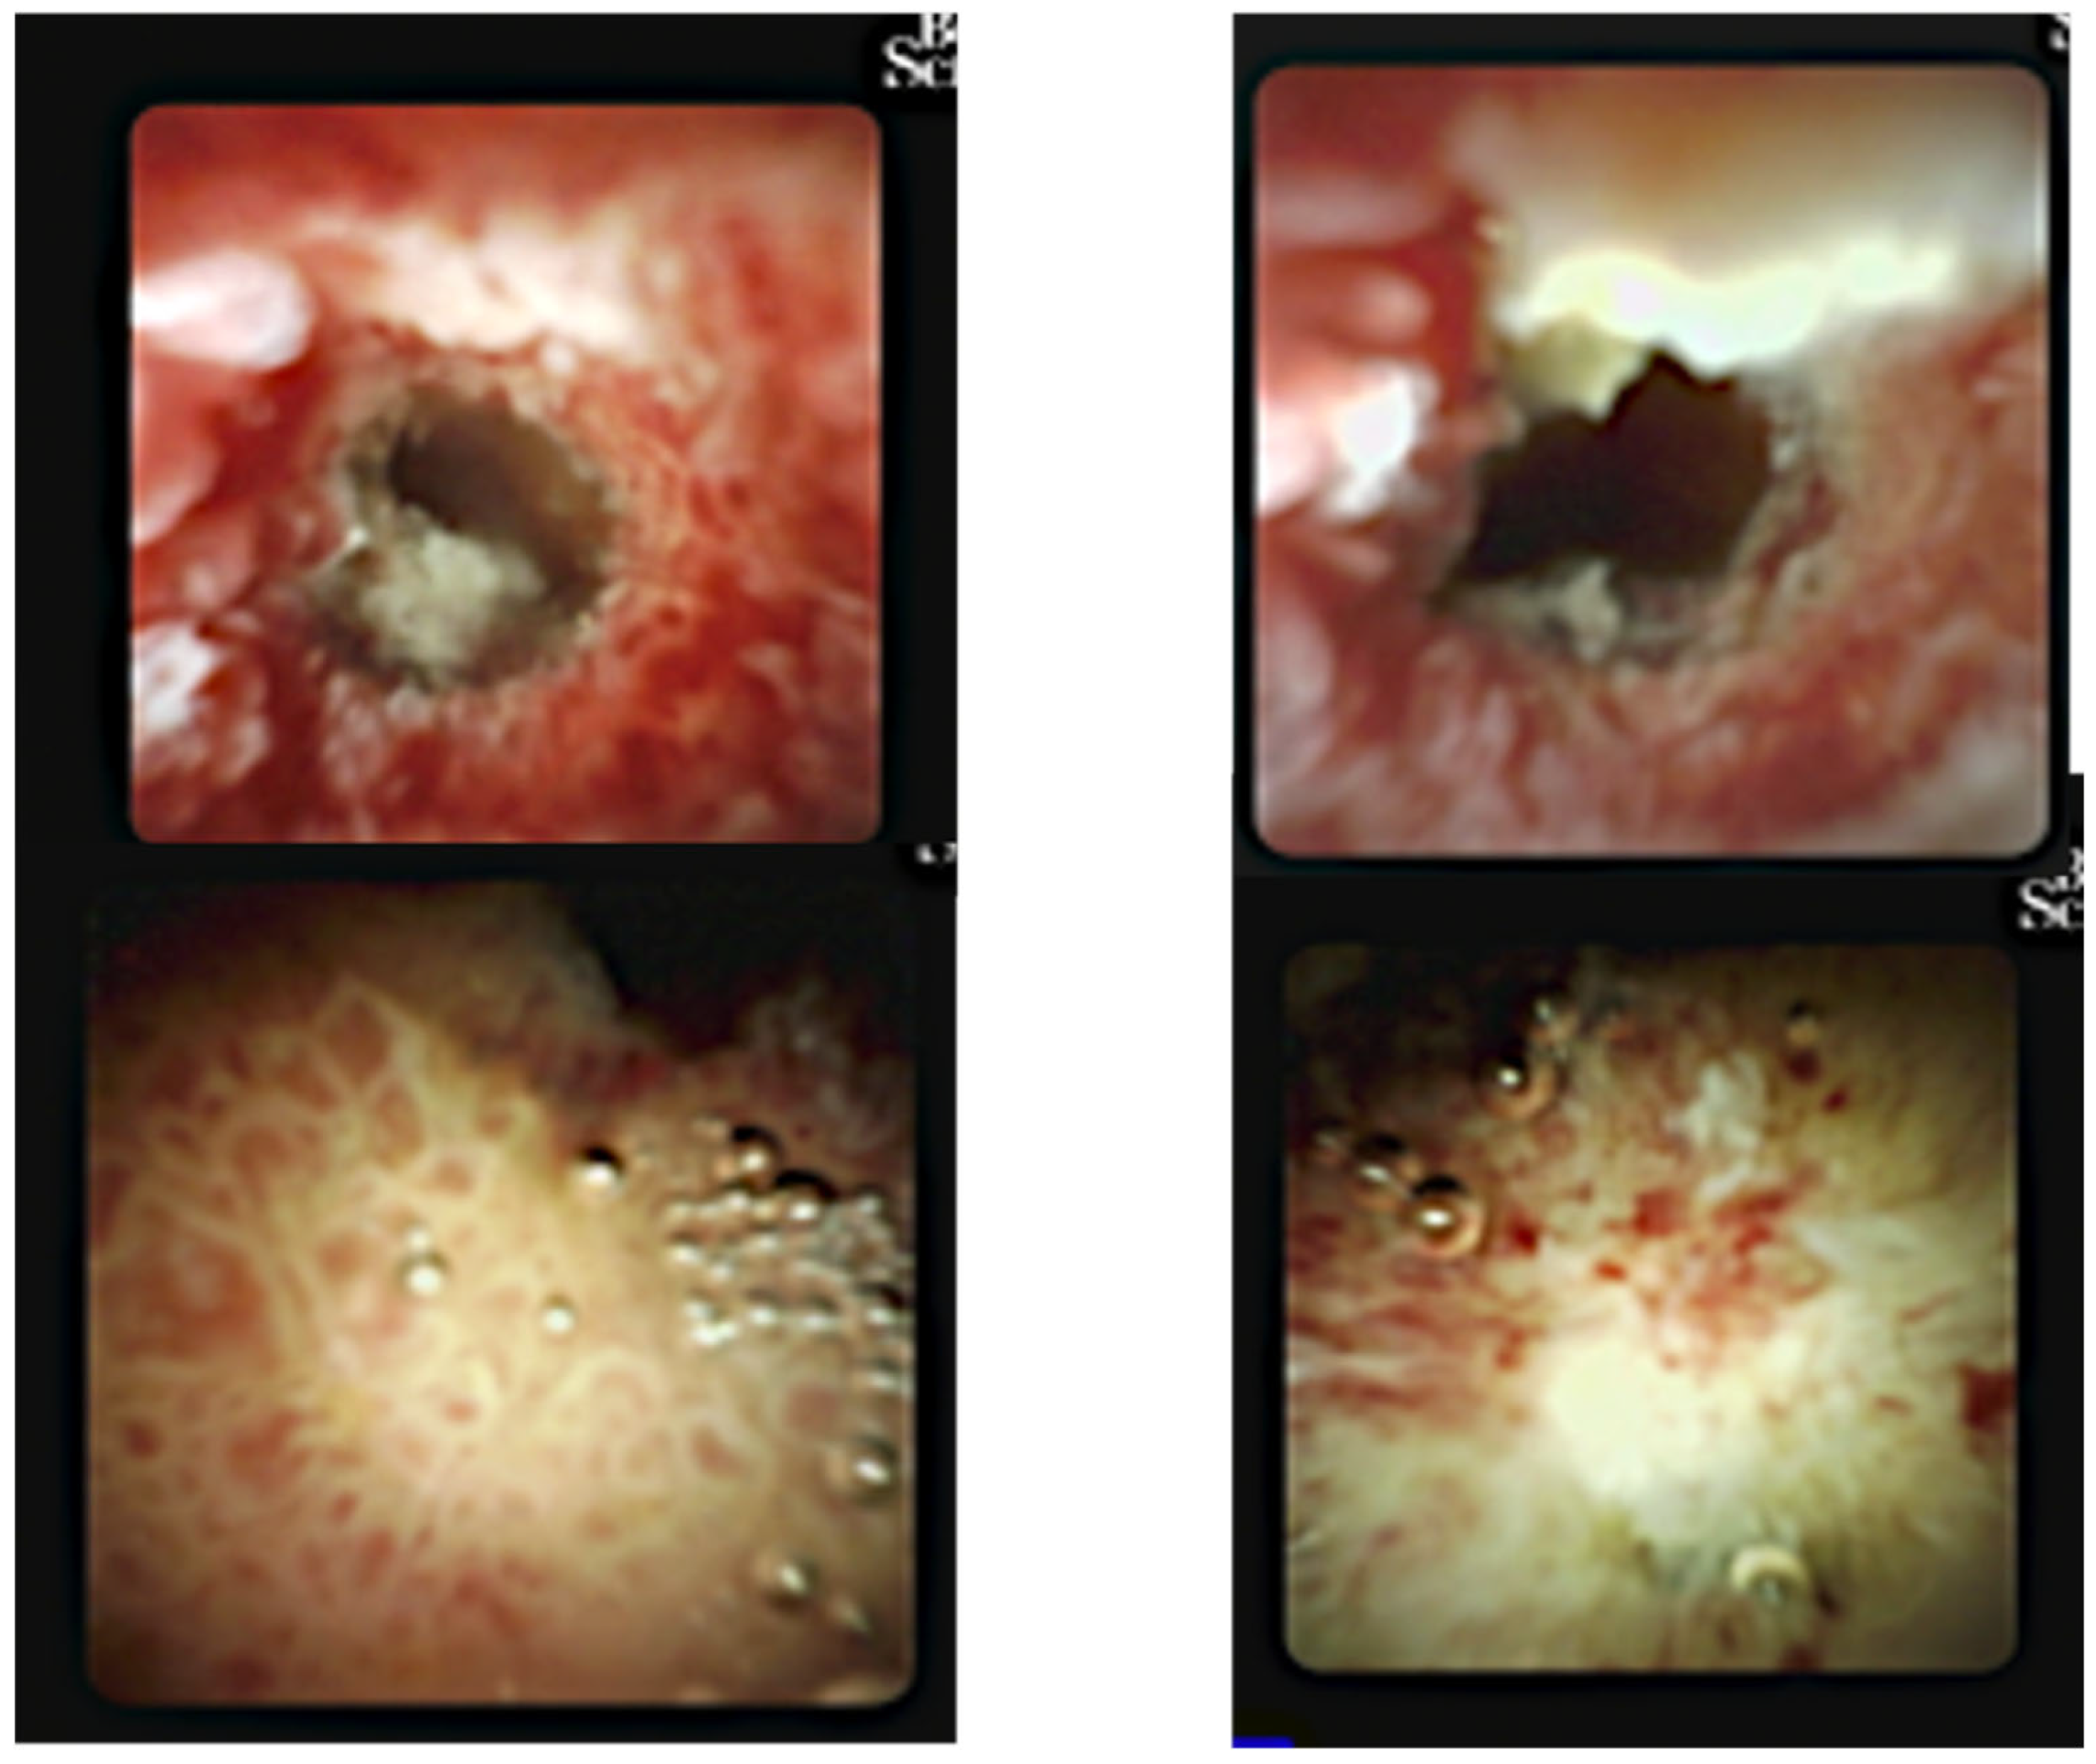

- 14.02: First ERCP showed normal bile ducts and papilla, no strictures or filling defects (Figure 2A).

- 18.02: Second ERCP again found no obstructive lesion; a 10Fr/10cm plastic stent was placed empirically (Figure 2B). No clinical or biochemical improvement was observed.